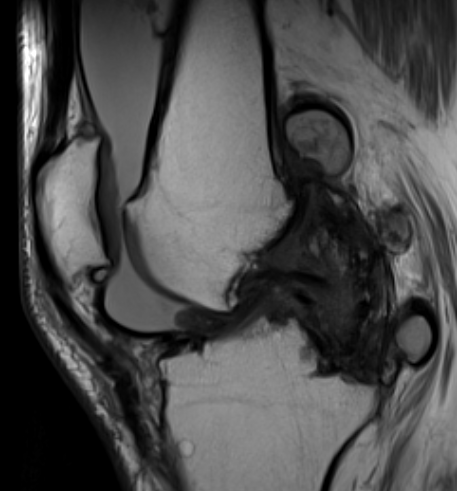

MRI

Synovial thickening

Hemosiderin

- low signal intensity on TI and T2 - "drop out" signals

- blooming on gradient echo

Diffuse PVNS with involvement of suprapatella pouch and posterior compartments, including posterior extra-articular

Severe diffuse PVNS with bony involvement